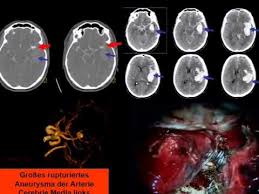

Kleines aneurysma im kopf. Ein Aneurysma vor allem im Gehirn kann angeboren sein. Häufig befinden sich die Aneurysmen im Kopf an den Aufzweigungen Bifurkationen der Arterien. Schließlich kann das Aneurysma platzen und eine unter Umständen lebensgefährliche Blutung im Kopf bewirken.

Für die meisten Patienten ist aber weit relevanter ob sie jung. Da das Schiff beginnt sich aufzublähen wird es wahrscheinlicher zu platzen. Platzt ein Aneurysma auf kann eine gefährliche Blutung entstehen die im schlimmsten Fall für den Betroffenen den Tod bedeutet.

Schließlich kann das Aneurysma platzen und eine unter Umständen lebensgefährliche Blutung im Kopf bewirken.

Ein Aneurysma vor allem im Gehirn kann angeboren sein. Da das Schiff beginnt sich aufzublähen wird es wahrscheinlicher zu platzen. Niemand kann vorhersagen wann ein Aneurysma platzt und Leck Blut in die umliegenden Gebiete. Solange ein Aneurysma noch klein und intakt ist das Gefäß also keine Risse hat verursacht es häufig keinerlei oder nur unspezifische Beschwerden wie Kopfschmerzen oder Übelkeit. Wenn ein Blutgefäß erweitert oder Ballons durch Schwächung Wände heißt es ein Aneurysma. Je nach Größe und Lage des Aneurysmas im Gehirn können jedoch auch Beschwerden auftreten. Ein Aneurysma ist eine krankhafte Aussackung einer Schlagader. Fachleute gehen aber davon aus dass Aneurysmen mit einem Durchmesser unter sieben Millimetern nicht sofort behandelt werden müssen sondern beobachtet werden können. Je nach Größe und Ort sind weitere Symptome möglich.

Nicht rupturierte intrakranielle Aneurysmen finden sich bei etwa drei Prozent der Erwachsenen. Ein Aneurysma ist eine krankhafte Gefäßausstülpung also eine örtlich begrenzte Erweiterung einer Arterie. Ein Aneurysma ist eine krankhafte Gefäßausstülpung die sich an den hirnversorgenden Gefäßen zumeist an Gefäßaufzweigungen befindet. Die meisten Gefäßaussackungen im Kopf entdecken Ärzte durch Zufall oder weil sie Symptome wie beispielsweise Doppeltsehen verursachen. Täglich im Kühlschrank aufbewahren. Aber es lässt sich nicht ganz ausschließen dass auch solche kleinen Aneurysmen reißen. Niemand kann vorhersagen wann ein Aneurysma platzt und Leck Blut in die umliegenden Gebiete.